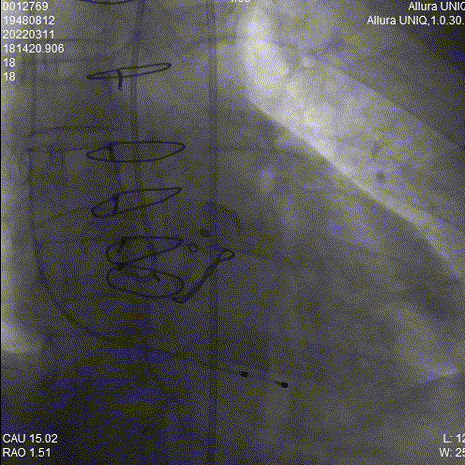

主动脉根部造影

对侧Snare辅助

Snare辅助过弓